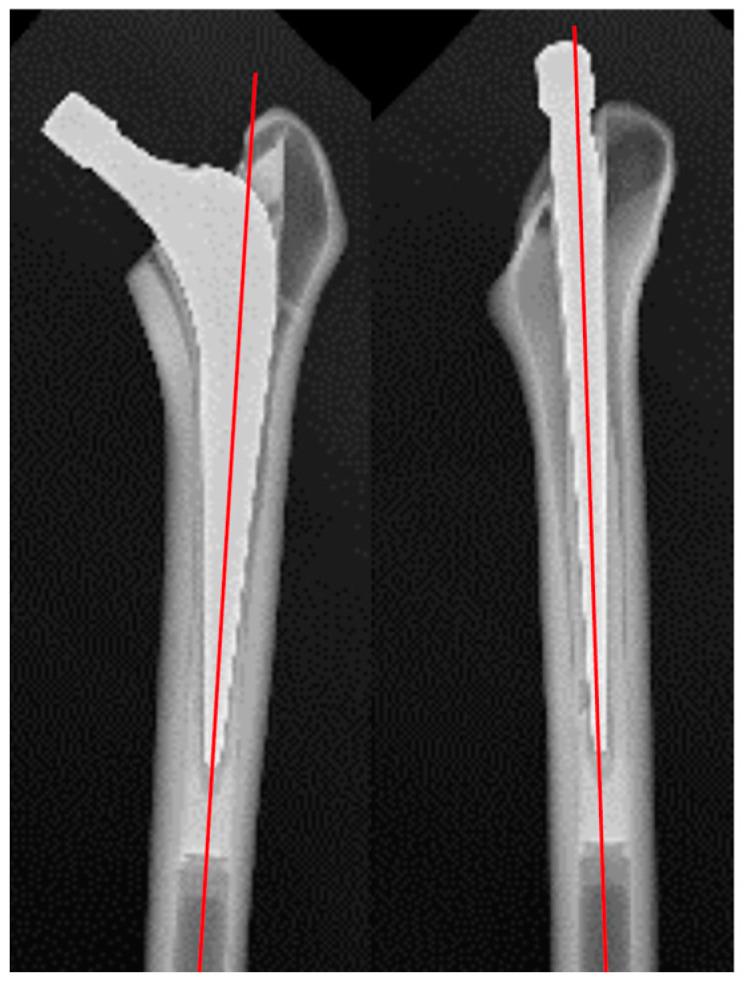

: The increasing number of aging patients with total hip arthroplasties (THA) causes an increased incidence of periprosthetic fractures (PPF). The study aimed to evaluate the impacts of two different materials in the same-sized cemented stems on PPF in bone models. : This study compared the maximum rotational torque leading to PPF when stems made of cobalt-chromium-molybdenum (Co-Cr-Mo) alloy and stainless use steel (SUS) were implanted using simulated bone models (Sawbones, 3403). The maximum destruction torque was compared statistically for each material (Co-Cr-Mo alloy vs. SUS stainless steel) in this model, and fracture patterns were examined. : The PPF occurred with a spiral propagation from the proximal femur towards the diaphysis, with breakage occurring near the distal end of the stem. There were no significant differences in the destruction torque values between the Co-Cr-Mo alloy (103.0 ± 14.9 Nm) and SUS (98.7 ± 15.1 Nm) samples ( = 0.575). The fractures using the bone models exhibited similar patterns in all specimens, resembling clinical PPF fracture types clinically, specifically Vancouver classification B2. : The comparison of the maximum destruction torques of the Co-Cr-Mo alloy and SUS cemented stems in simulating PPF showed no significant differences. The results suggest that the materials of the cemented stems might not significantly affect the occurrence of PPF in THA.

PPF从股骨近端向骨干呈螺旋状扩展,在柄的远端附近发生断裂。Co-Cr-Mo合金样本(103.0±14.9 Nm)和SUS样本(98.7±15.1 Nm)的破坏扭矩值无显著差异(P = 0.575)。使用骨模型的骨折在所有标本中表现出相似的模式,临床上类似于临床PPF骨折类型,特别是温哥华分类B2。